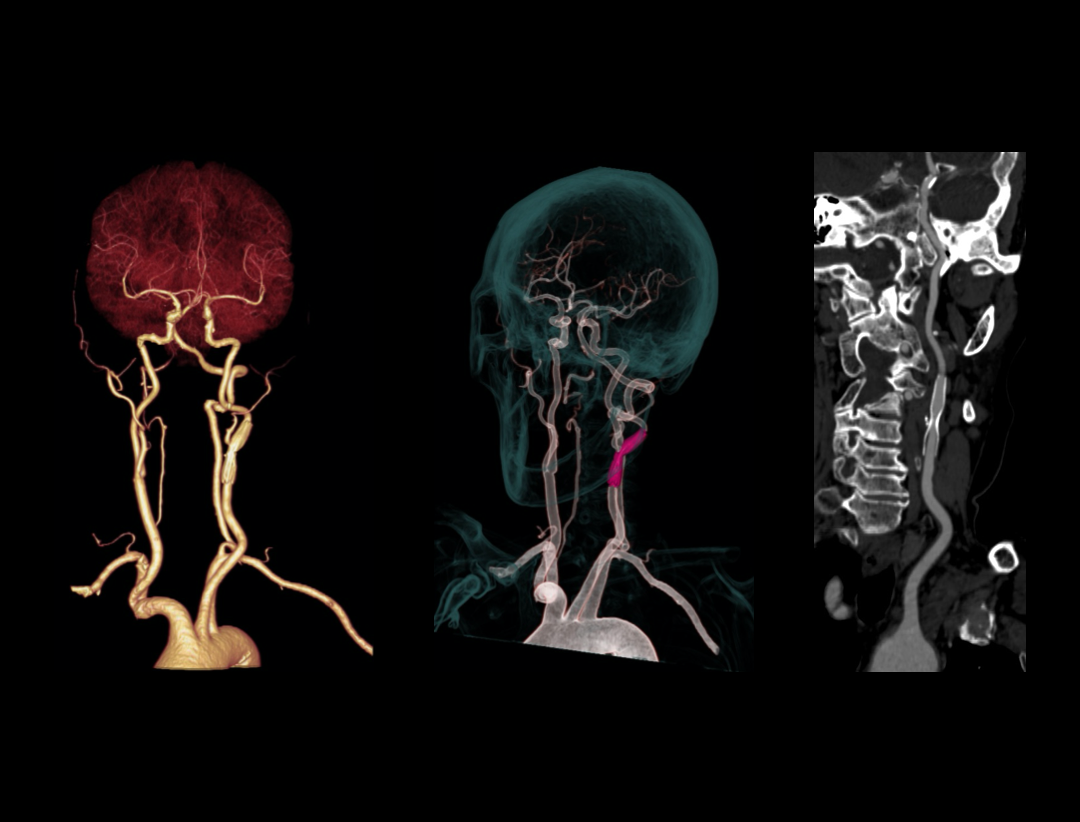

Carotid CTA